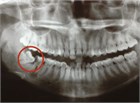

典型的には患者は17~29歳で,一部萌出または埋伏した第3大臼歯(智歯)周囲の疼痛を伴う腫脹および感染徴候を主訴に受診することが多い.同部位から滲出した膿による嫌な味がする場合もある.疼痛は非常に強く,頸部,咽頭,耳,口腔底に放散することがある.時に開口障害(顎が数mm以上開けられない)や咬合時の痛みがある.感染部は発赤,腫脹があり,歯肉弁の下に,一部萌出した歯が認められることがある(47.1).歯肉弁を引っ張ると排膿がみられることがある.歯の打診時には疼痛はないことが多い.